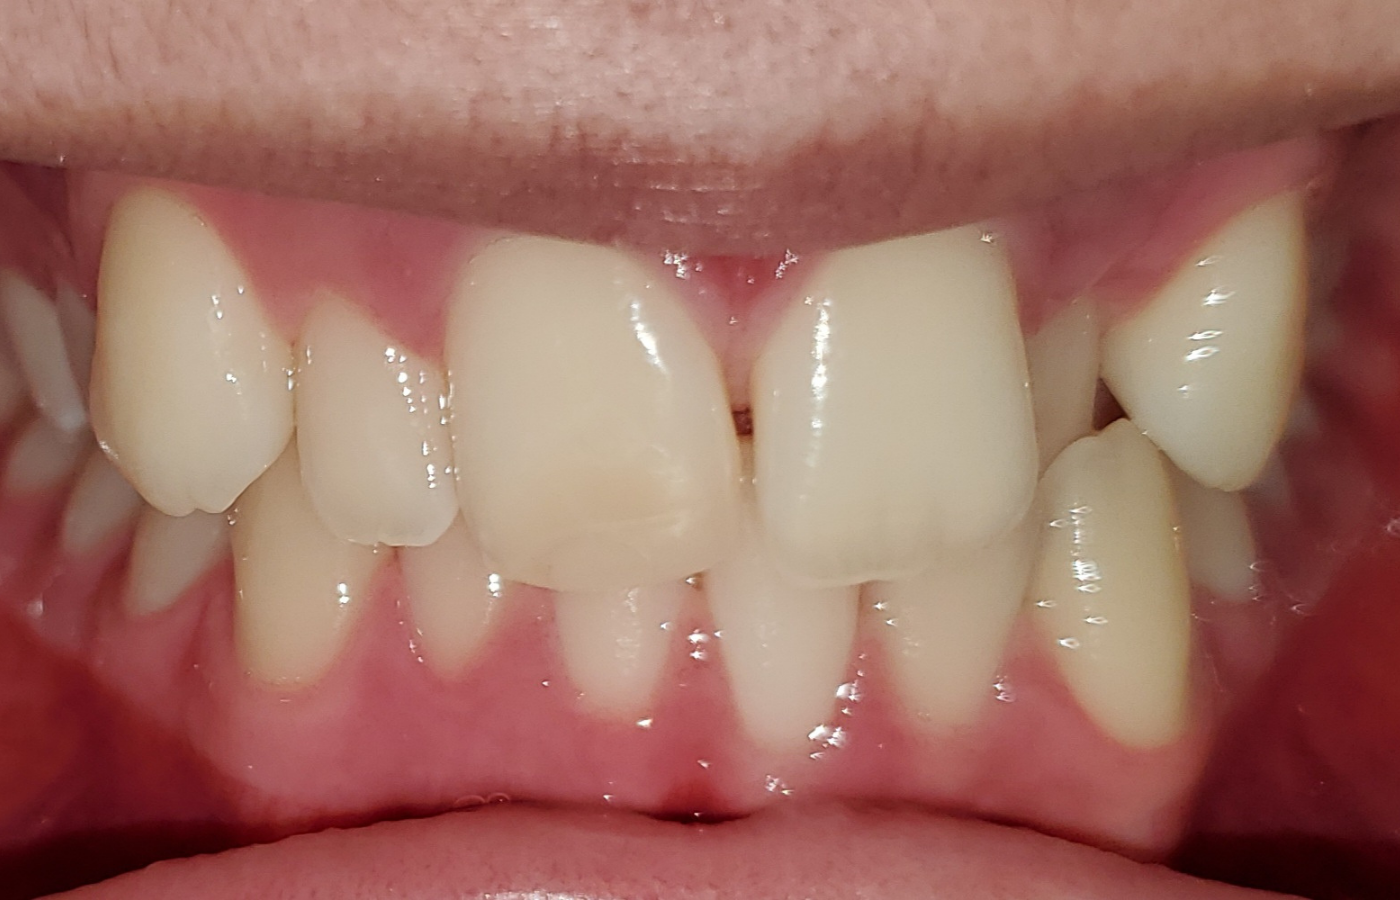

This case review features a patient of Esther Jeong, DDS, at Willow Family Dentistry in Wylie, TX. The development of the patient’s dental arches didn’t allow adequate space for her adult dentition to express fully, leading to a mix of Class II and Class III contacts, a trapped mandible, and a crossbite that caused her significant discomfort.

The patient wasn’t confident in her teeth and often smiled without showing her teeth. And when it came to chewing, she was constantly on edge because of how often her misaligned teeth caused her to bite her lip.

When this patient came to see Dr. Jeong, it was clear that orthodontic intervention was needed.